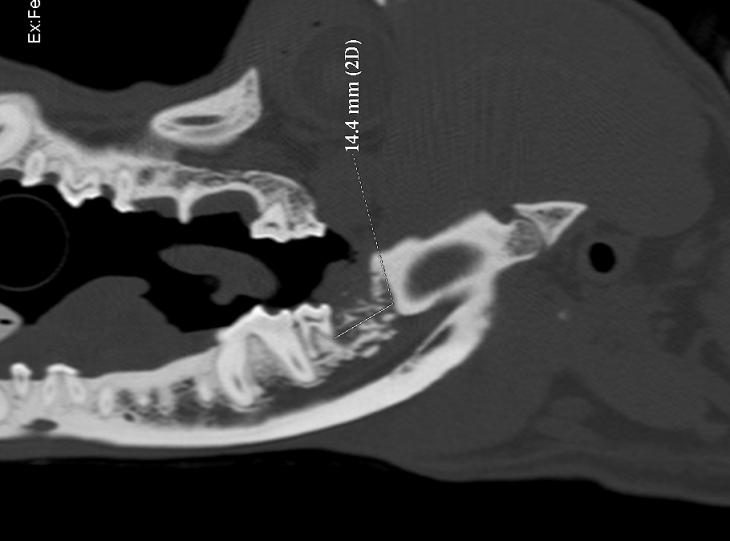

A CT scan was performed which allowed accurate assessment of the limits of tumour invasion and consequent surgical margins

Sagittal view of a CT scan showing the presence of an invasive mass at the level of the right second mandibular molar in a dog

These were drawn onto a sagittal view of the affected mandible allowing detailed preoperative planning of the resection.